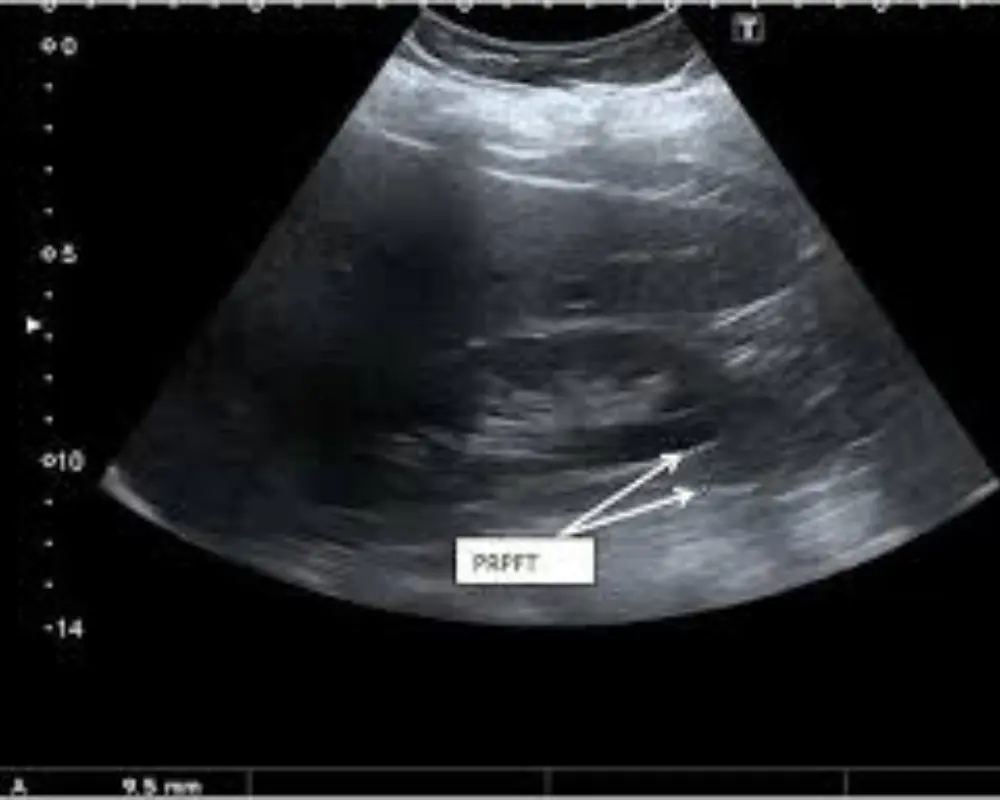

Soft Tissue Ultrasound

This ultrasound scan evaluates muscles, tendons, and soft tissues to detect injuries, swelling, or abnormalities, helping guide accurate diagnosis and effective treatment.